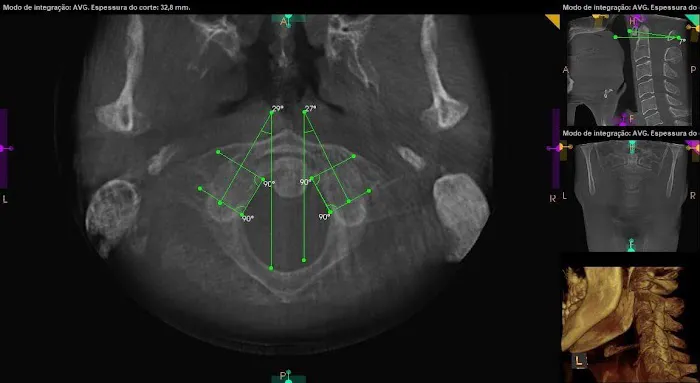

At Los Angeles Upper Cervical, the focus is on a unique and highly effective form of chiropractic care known as upper cervical chiropractic. This specialized approach centers on the crucial connection between the uppermost vertebrae of your spine (the atlas and axis) and your overall nervous system health. Misalignments in this delicate area can have far-reaching effects on your body, impacting everything from pain levels and mobility to neurological function and even your body's ability to heal itself. With a commitment to precision and a deep understanding of the body's intricate systems, Dr. Bello and his team offer a level of care that stands apart.

- Upper Cervical Chiropractic Adjustments: Precise, gentle adjustments focused on the atlas and axis vertebrae, aiming to correct misalignments that can impact the entire nervous system and body. These adjustments are often described as remarkably gentle yet profoundly effective.

- TMJ (Temporomandibular Joint) Disorder Treatment: Targeted care to alleviate jaw pain and dysfunction, which can often be linked to upper cervical misalignments. Patients have reported significant improvement in their TMJ symptoms after receiving care here.

- Detailed Scans and Diagnostics: Utilizing advanced imaging techniques to thoroughly assess the upper cervical spine and surrounding structures, guiding precise and effective treatment plans.

Jul 01, 2025 · Steve ImI came to see Dr Bello after a car accident last year. I was stiff and in a lot of pain. I wanted to make sure that if I saw someone after my accident they would know what they were doing and wouldn’t make me worse. Desperate for relief, I turned to Dr. Bello on a friend's recommendation. The accident affected my head, neck, back, hips, and threw off my jaw. His passion for upper cervical chiropractic care was evident from the start.Dr. Bello took detailed scans of my upper cervical vertebrae and head, which guided his treatment. He explained how neck displacements could impact the rest of my body. His targeted care began to alleviate my pain from day 1, including my jaw issues!! Nothing has ever helped my TMJ which was very much exacerbated atfter the accident.Beyond his chiropractic expertise, Dr. Bello collaborated with other practitioners. In the same building, I received acupuncture from Jessica at LaLuz Wellness, which helped with chronic pain and soft tissue injuries and trauma symptoms from the accident. Additionally, Jon Haupers LENS neurofeedback at Neurobalance addressed my TBI.This combination of treatments worked wonders. My pain lessened, my mobility improved, and I started to feel like myself again. Dr. Bello’s holistic approach, along with Jessica's and Jon's treatments, provided a comprehensive recovery plan.I would wholeheartedly recommend Dr. Bello . His genuine care, expertise, and dedication, combined with the collaborative efforts of his team, have made a profound difference in my life. I am incredibly grateful for their support and the thorough approach that has led to my healing.

Aug 16, 2024 · Heidi IreneI’ve been seeing Dr. Bello since January and I can’t say enough how much he has helped me. Prior to January, I was having horrible jaw pain that would last throughout the day and made eating a miserable experience. He did a 3D scan that showed the problem was actually my neck and explained how long it would take for it to improve with his adjustments.At first, I had to visit him twice a week because my neck was in such bad shape, but now I only have to see him once every three weeks and my neck muscles have gotten stronger and stabilized a lot. Still have a ways to go but I’m beyond happy with how these 7 months of care have gone.